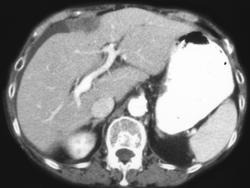

Gastric Varices (dual Phase- Seen Best in Portal Phase)